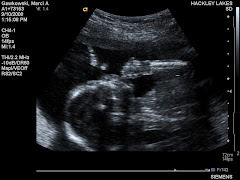

Cooper Peter Gawkowski

Cooper is only two months old and here I am finally getting him on the blog!!